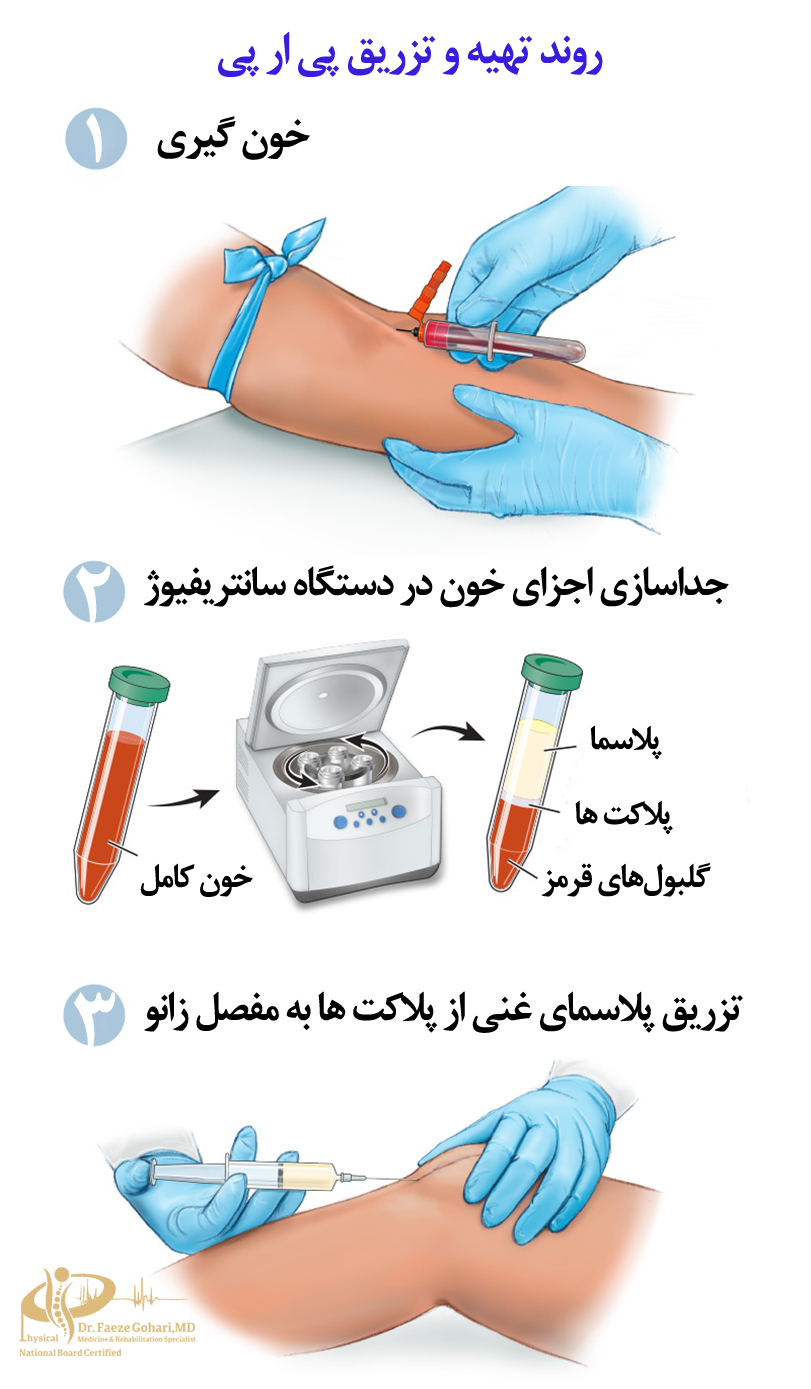

روند درمان زانو با پی ار پی چگونه است؟

نحوه تزریق پی ارپی به زانو

برای تزریق پیآرپی، توصیه میشود بیمار حدود ۱ تا ۱.۵ ساعت پیش از زمان تعیینشده در مطب حضور داشته باشد تا فرایند خونگیری و آمادهسازی PRP بدون وقفه و بادقت کامل انجام شود.

تهیه پیآرپی معمولاً در همان کلینیک یا مطب و با استفاده از دستگاه سانتریفیوژ صورت میگیرد و نیازی به ارسال نمونه به آزمایشگاه جداگانه نیست. ازآنجاکه اثربخشی پیآرپی بهتازگی و فعالبودن فاکتورهای آن وابسته است، باید حداکثر ظرف چند ساعت پس از آمادهسازی تزریق شود. در ادامه روند تزریق توضیح داده شده است.

خونگیری

ابتدا مقدار مشخصی از خون بیمار (معمولاً بین ۱۵ تا ۳۰ میلیلیتر) از طریق ورید بازو گرفته میشود. این خون پایهای برای تهیه پیآرپی خواهد بود.

تهیه پی آر پی

خون گرفتهشده بلافاصله در دستگاه سانتریفیوژ قرار میگیرد تا پلاکتها از سایر اجزای خون جدا شوند. این فرایند معمولاً در دو مرحله انجام میشود تا پیآرپی با غلظت بالای پلاکت و حداقل ناخالصی به دست آید. همچنین، نوع و غلظت نهایی PRP بسته به نوع آسیب میتواند شخصیسازی شود؛ برای مثال، در برخی موارد از فرمهای دارای گلبول سفید و در موارد دیگر از فرمهای بدون آن استفاده میشود تا با نیاز درمانی بیمار هماهنگ باشد.

غلظت پلاکتها باید ۴ تا ۶ برابر بیشتر از پلاسمای معمولی باشد. این غلظت به پزشک کمک میکند تا حداکثر اثربخشی را برای بهبود بافتها ارائه دهد.